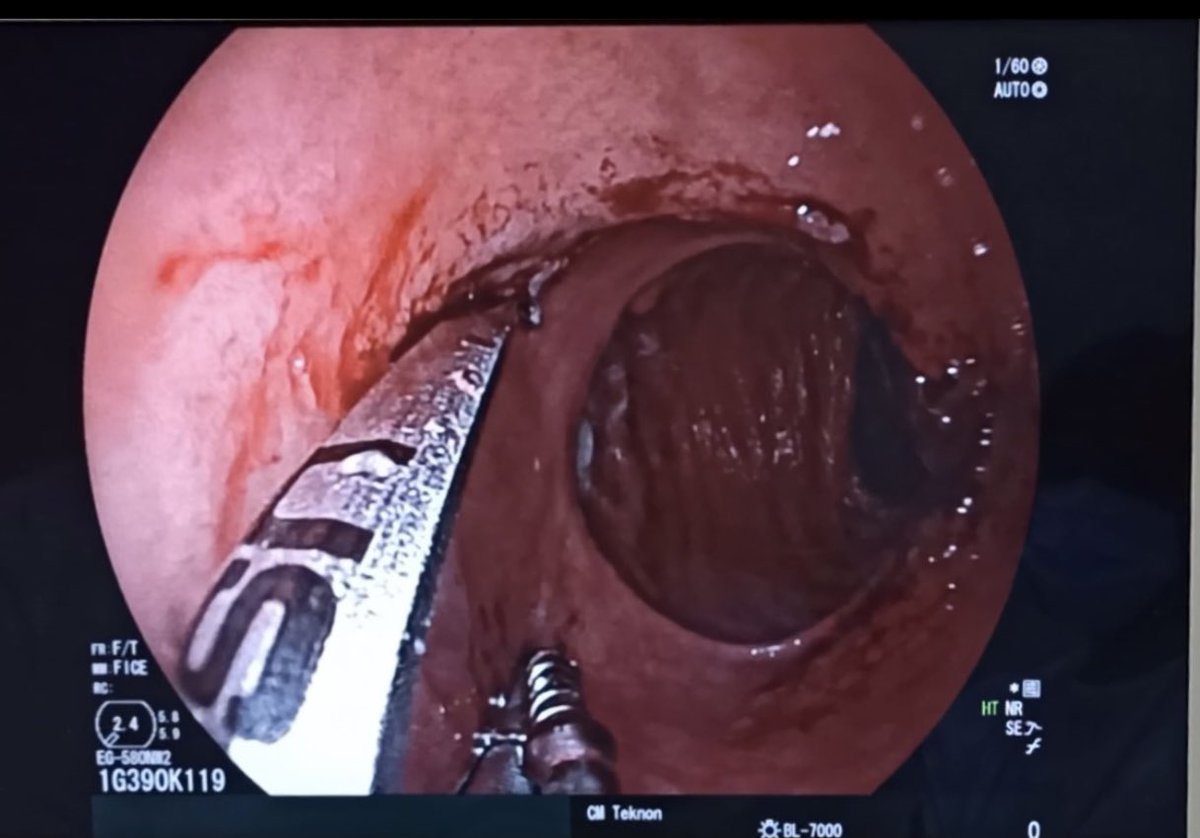

2nd and 3rd bites. Less than 10 minutes procedure. Safe, clean and effective. @Clinica_Teknon #bariatricendoscopy #bypassreparation #ROSEprocedure #obesidad #endoscopia @EEndoscopia @TerapiasObesid

La reparación endoscópica del #bypass con plicatura es una realidad, segura, rápida y efectiva @SEEDendoscopia @SociedadSeedo @aec_obesidad @secojoven @sa6ater @EEndoscopia @Clinica_Teknon

Laparoscopic Gastric Plication reparation with Endoscopic Plication with the @USGIMedical device. @EEndoscopia @Clinica_Teknon @SEEDendoscopia @secojoven @aec_obesidad @SociedadSeedo @Clinica_Teknon @EndoscopicTreat @sa6ater. Great work to all the team. 7%TBWL in 6 days.